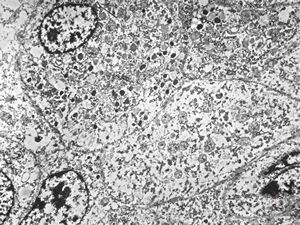

F,68y. | APUD carcinoma

F,68y. | APUD carcinoma (Bodian siver impregnation)